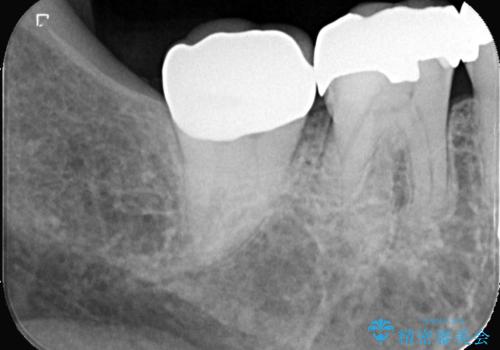

【オールセラミッククラウン】銀歯の下が虫歯に!

- 当院にメインテナンスで通っていただいている患者様です。銀歯の下の虫歯が大きくなってきたので、治療を行いました。

銀歯を外し虫歯を除去後、オールセラミッククラウンで治療を行いました。

銀歯は錆びる金属が使用されており、型取りの材料も変形がある材料になってしまうので、再び虫歯になってしまっている患者さんが沢山おられます。

当院は適合にこだわったセラッミク治療を行っているので、虫歯の再発のリスクを大きく下げる事が可能です。